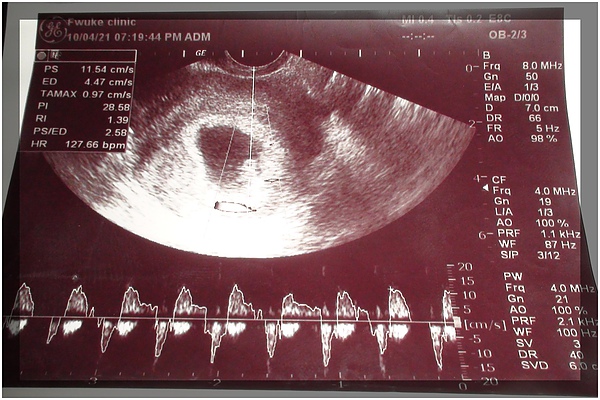

心情故事 每個經歷都變成無價資產 懷孕初期第七週的變化 妞媽lisa Li X 妞爸169 分享愛

心情故事 每個經歷都變成無價資產 懷孕初期第七週的變化 妞媽lisa Li X 妞爸169 分享愛

心就在這裡停泊吧 藏了好久的祕密 肚子裡的小胎寶滿三個月了 孕4週 孕8週

心就在這裡停泊吧 藏了好久的祕密 肚子裡的小胎寶滿三個月了 孕4週 孕8週

孕 6週 10週 戰戰兢兢的懷孕初期 依芙琳看世界 痞客邦

7w5 4w5 第一次產檢 5c9